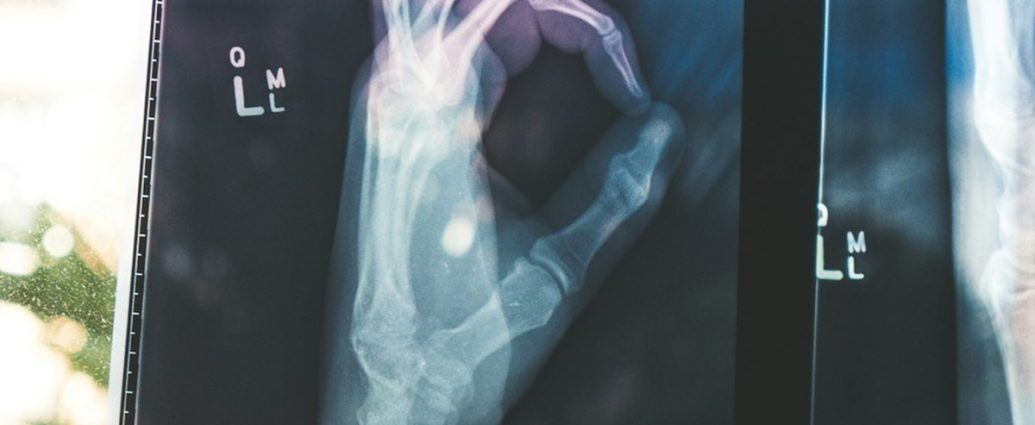

피로골절은 외부의 강한 충격으로 뼈가 ‘뚝’ 부러지는 일반적인 골절과는 다릅니다. 뼈의 특정 부위에 반복적이고 지속적인 스트레스(부하)가 가해지면서 뼈 조직에 미세한 손상이 축적되고, 결국 실금처럼 작은 균열이 생기는 부상을 말하죠. 마치 금속이 반복적인 힘에 의해 서서히 파괴되는 ‘피로 파괴’와 유사합니다.

우리 몸의 뼈는 스스로 회복하는 능력이 있지만, 회복 속도보다 손상이 더 빠르게 진행되면 피로골절로 이어질 수 있습니다. 특히 체중 부하가 많은 다리 부위, 즉 정강이뼈(경골), 발등뼈(중족골), 발뒤꿈치 등에서 흔하게 발생합니다.